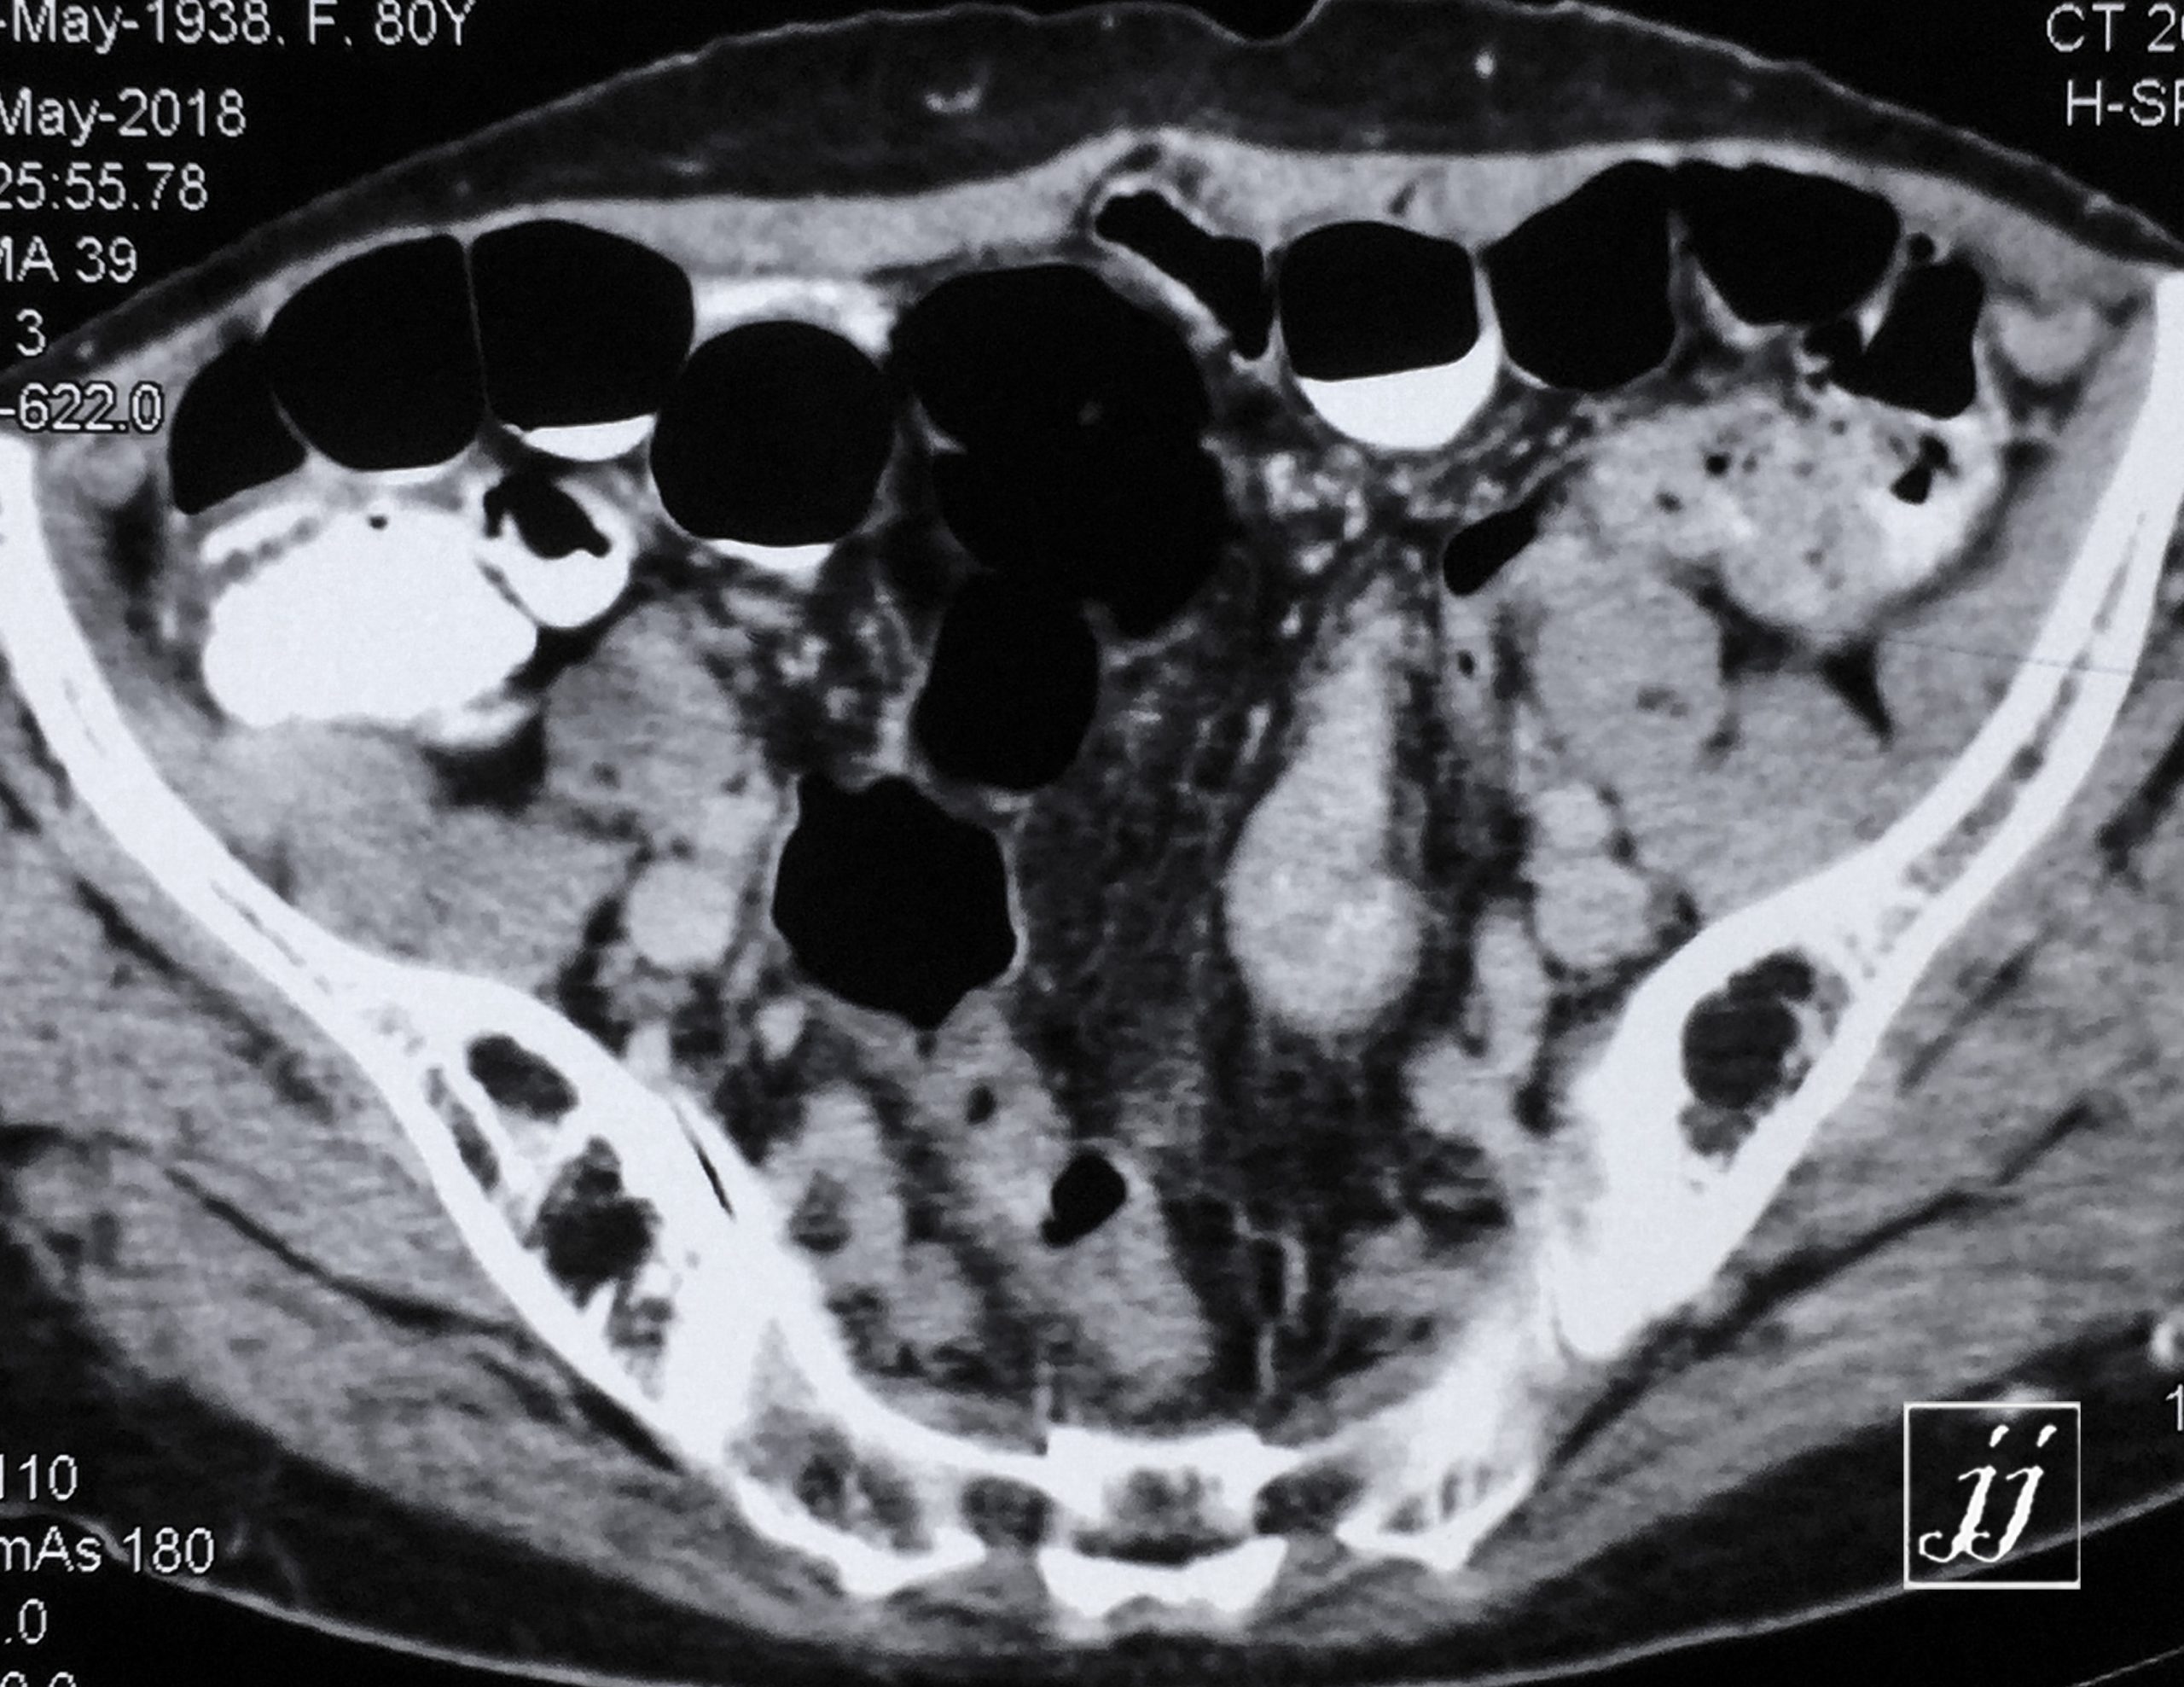

Abdomen- left kidney parapelvic cyst, and midline hernia (13)